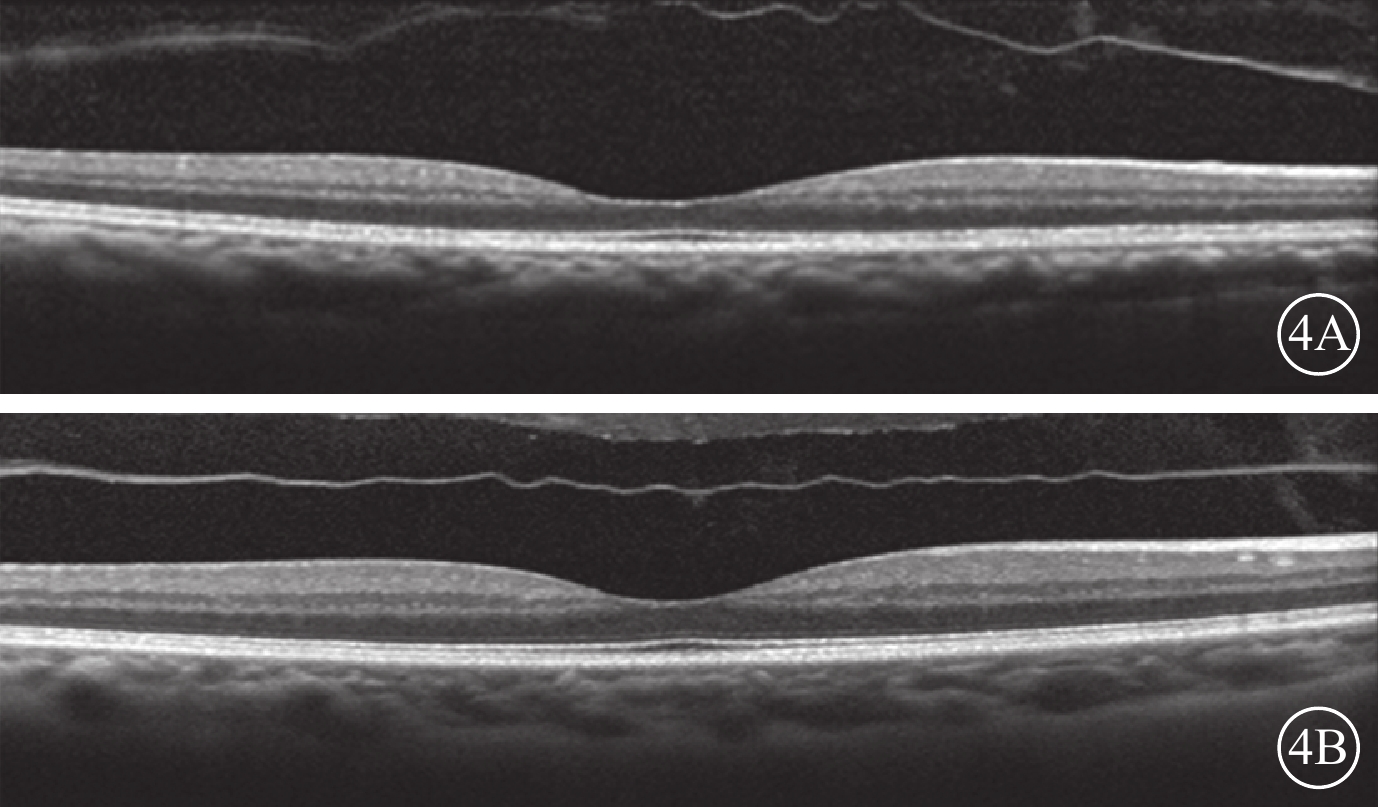

所有患者均采用3+PRN的方式接受玻璃體腔注射抗VEGF藥物治療。治療前采用OCT觀察患者雙眼的VMI情況。以中心凹為中心,掃描黃斑區,使用高速模式。(1)體積掃描:ART疊加次數9次,97線掃描線,20°×20°;(2)十字掃描:ART疊加次數36次,2線掃描線,20°×20°。將存在玻璃體黃斑粘連(VMA)、黃斑前膜(MEM)、完全性玻璃體后脫離(C-PVD)定義為VMI異常。以玻璃體粘附在中心凹中心3 mm直徑內,但部分玻璃體視網膜分離為VMA;并根據OCT圖像上玻璃體與黃斑部粘附的直徑大小將VMA分為局灶型(≤1500 μm)和廣泛型(>1500 μm)[17]。以鄰近或貼覆在黃斑前、較玻璃體后界膜厚且反射性強的組織為MEM[18]。以玻璃體后界膜高起,與視網膜黃斑無粘附為C-PVD[19-21]。34只研究眼中,存在VMI異常(圖1)12只眼。其中,廣泛型VMA 8只眼,局灶型VMA 3只眼,MEM 1只眼;合并存在局灶型VMA、MEM 1只眼。34只對照眼中,存在VMI異常(圖2)12只眼。其中,廣泛型VMA 7只眼,局灶型VMA 2只眼,C-PVD 2只眼,MEM 1只眼。治療后隨訪觀察12~26個月,平均隨訪時間16.4個月。隨訪期間每月用隨訪模式進行雙眼OCT檢查。對比分析患者雙眼治療前后VMI的變化情況。

VMI異常的對照眼OCT像。2A. 黃斑中心凹區域局灶型VMA(白箭);2B. 黃斑區廣泛型VMA(白箭)

VMI異常的對照眼OCT像。2A. 黃斑中心凹區域局灶型VMA(白箭);2B. 黃斑區廣泛型VMA(白箭)

所有患者均采用3+PRN的方式接受玻璃體腔注射抗VEGF藥物治療。治療前采用OCT觀察患者雙眼的VMI情況。以中心凹為中心,掃描黃斑區,使用高速模式。(1)體積掃描:ART疊加次數9次,97線掃描線,20°×20°;(2)十字掃描:ART疊加次數36次,2線掃描線,20°×20°。將存在玻璃體黃斑粘連(VMA)、黃斑前膜(MEM)、完全性玻璃體后脫離(C-PVD)定義為VMI異常。以玻璃體粘附在中心凹中心3 mm直徑內,但部分玻璃體視網膜分離為VMA;并根據OCT圖像上玻璃體與黃斑部粘附的直徑大小將VMA分為局灶型(≤1500 μm)和廣泛型(>1500 μm)[17]。以鄰近或貼覆在黃斑前、較玻璃體后界膜厚且反射性強的組織為MEM[18]。以玻璃體后界膜高起,與視網膜黃斑無粘附為C-PVD[19-21]。34只研究眼中,存在VMI異常(圖1)12只眼。其中,廣泛型VMA 8只眼,局灶型VMA 3只眼,MEM 1只眼;合并存在局灶型VMA、MEM 1只眼。34只對照眼中,存在VMI異常(圖2)12只眼。其中,廣泛型VMA 7只眼,局灶型VMA 2只眼,C-PVD 2只眼,MEM 1只眼。治療后隨訪觀察12~26個月,平均隨訪時間16.4個月。隨訪期間每月用隨訪模式進行雙眼OCT檢查。對比分析患者雙眼治療前后VMI的變化情況。

VMI異常的對照眼OCT像。2A. 黃斑中心凹區域局灶型VMA(白箭);2B. 黃斑區廣泛型VMA(白箭)

VMI異常的對照眼OCT像。2A. 黃斑中心凹區域局灶型VMA(白箭);2B. 黃斑區廣泛型VMA(白箭)